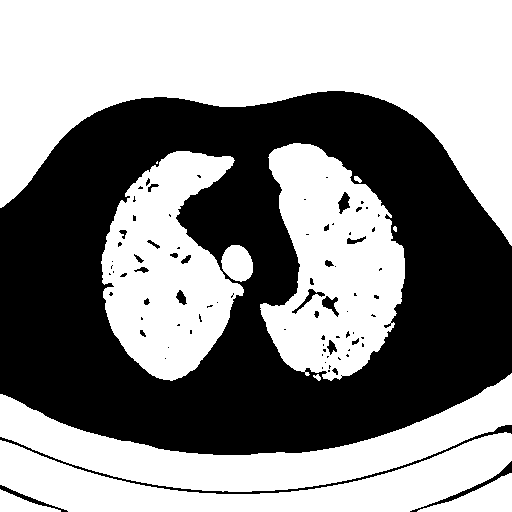

我在图像1上使用阈值掩码(图2)创建了以下图像(图3)。我试图使用opencv将图像3(肺)中央图像之外的所有像素转换为一种颜色(例如黑色)。基本上,这样我就只能在一个均匀的背景下(甚至是透明的)看到肺部的图像。我的问题是外部像素和图像3中肺内像素的相似性。这能用opencv吗?